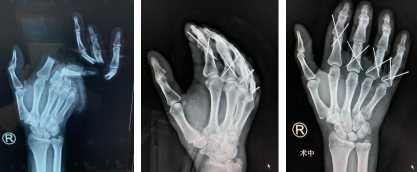

晚上6点半,黎医生手术团队为张大爷进行“右手2-5指清创,再植术+血管移植术”。术中,修剪断指残端及离断指体创缘,去除失活的皮肤组织,术中探查见:右示、中、环、小指近节指骨骨折伴部分缺损,双侧指固有动脉及双侧指固有神经断端长段挫伤伴缺损。右示、中、环、小指指深、指浅屈肌腱、指伸肌腱断端呈马尾状改变。用咬骨钳咬平残端骨质,手法复位右示、中、环、小指近节指骨骨折端,再依次修复断裂的肌腱和血管。手术进行到3个小时,接上的手指初次通血成功。经过8个多小时,手术顺利完成。